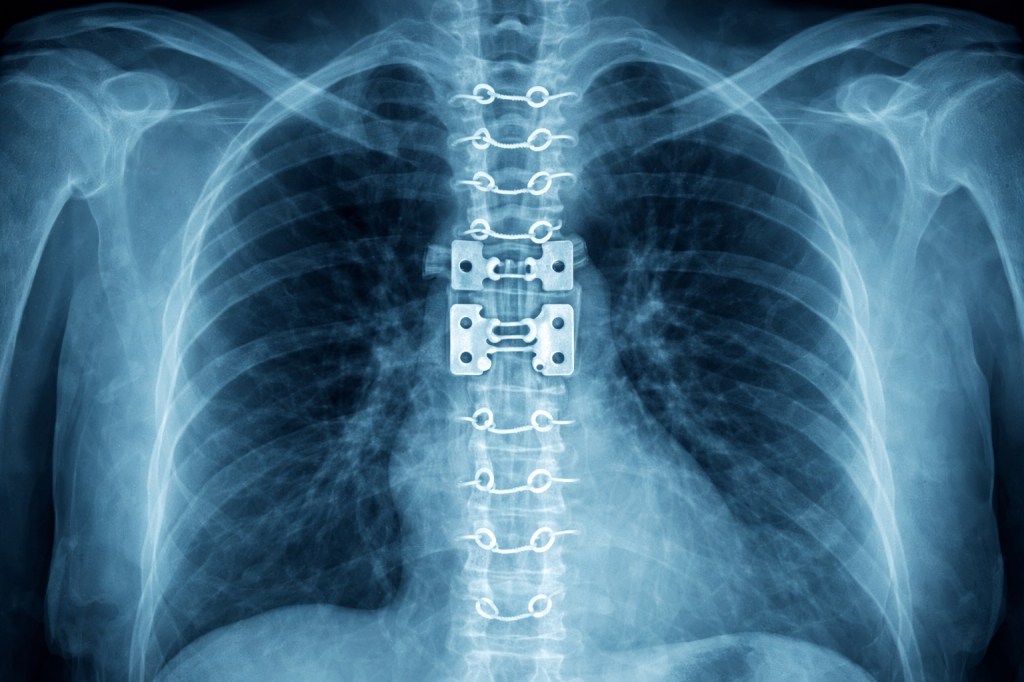

CHEST X RAYS

I remember getting chest x-rays. I would get these every day it seemed, but in this case the chest x-ray came to me. A technician wheels the x-ray machine into the room. A metal casing about one foot square, called the image receptor, was nestled between my back and my inclined bed. Then a heavy flexible lead shield was draped across my lap. The machine was lined up for the best position and the x-ray was taken.